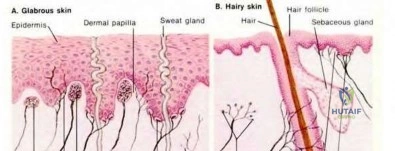

A 34-year-old female presents with severe pain in her thumb pulp, which is highly sensitive to cold, and excruciating point tenderness over the nail bed. There is a faint bluish discoloration under the nail plate. Radiographs show a small, smooth, scalloped radiolucency in the dorsal aspect of the distal phalanx. What is the most likely diagnosis?